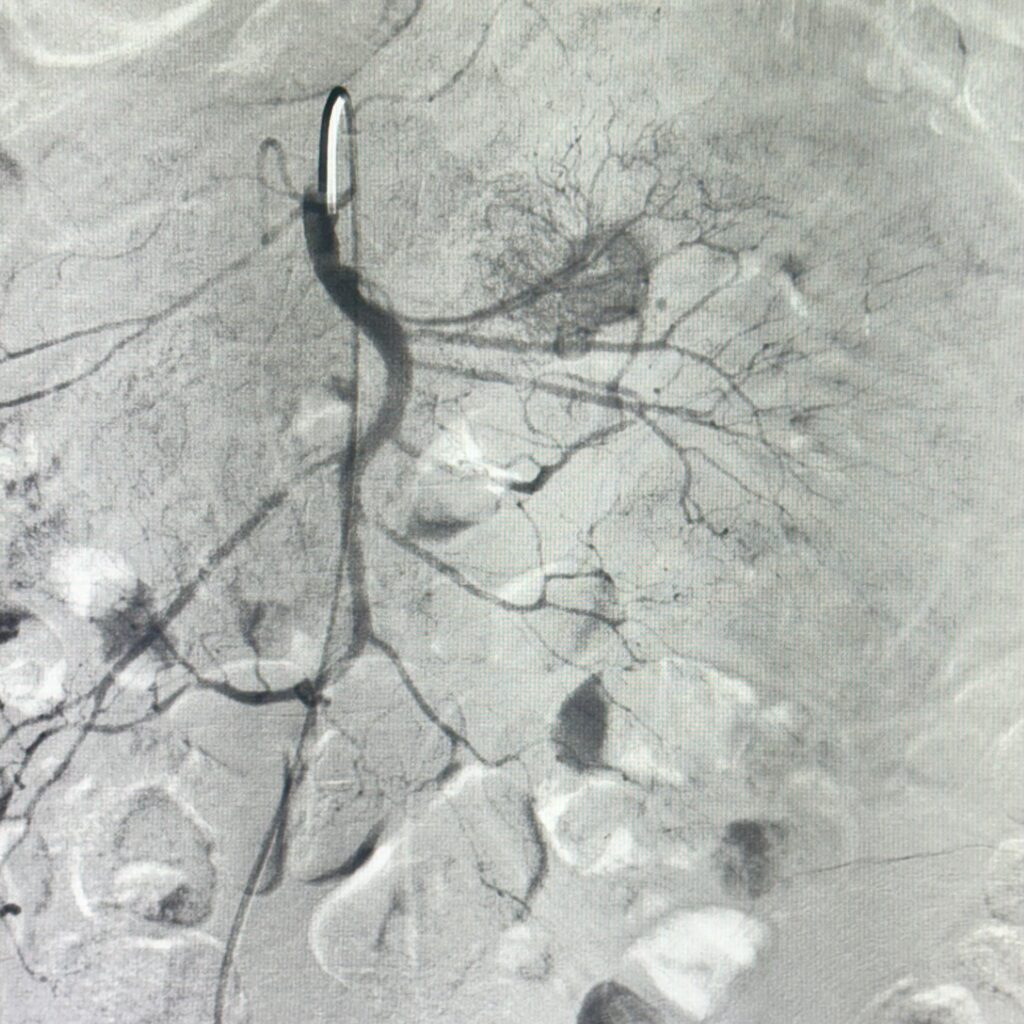

Figura 1: injectare în arteră mezenterică superioară cu evidențierea extravazării substanței de contrast

Video 1: injectare în arteră mezenterică superioară cu evidențierea angiodisplaziei jejunale

Discuţie caz nr 82: Pacient de 68 de ani internat cu 7 zile în urmă pentru hemoragie digestivă inferioară (hematochezie) și anemie secundară (Hb 7.1 mg/dL), care se accentuează progresiv în pofida transfuziilor repetate (Hb 4.9 mg/dL în ziua a cincea de internare).

Endoscopie Digestivă Superioară: fără particularități. Endoscopie Digestivă Inferioară: examinare efectuată până la nivelul colonului ascendent, evidențiază sânge proaspăt, fără a se putea identifica originea hemoragiei.

În ziua a opta de la internare se practică angiografie diagnostică de Arteră Mezenterică Superioară (aspect sugestiv de angiodisplazie jejunală), urmată de embolizare cu particule resorbabile (Gelaspon) a primului ram jejunal. Rezultat optim postprocedural: încetarea HDI, urmată de corectarea progresivă a sindromului anemic (Hb 9,0 mg/dL în ziua a patra postprocedural).